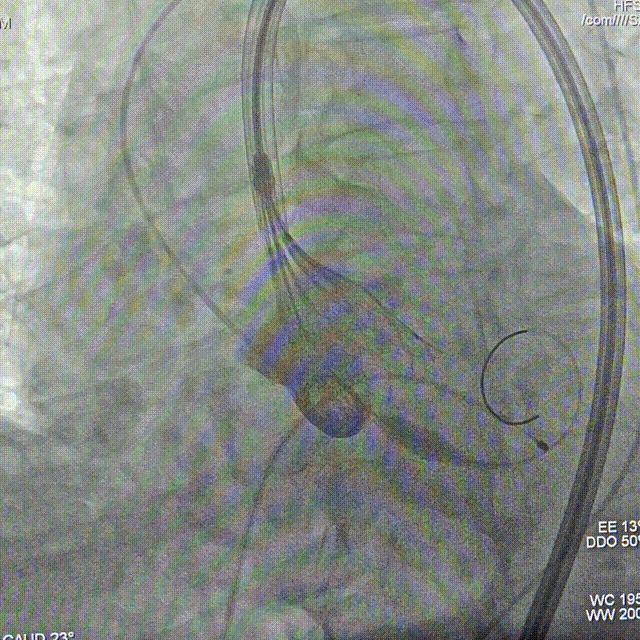

瓣膜0位定位释放

瓣膜稳定释放至全展开,无明显下滑,位置稳定

造影评估,瓣膜位于瓣下2mm形态稳定

左冠切线评估,小弯侧深度6mm

无张力脱钩,瓣膜无位移

最终造影,无瓣周漏